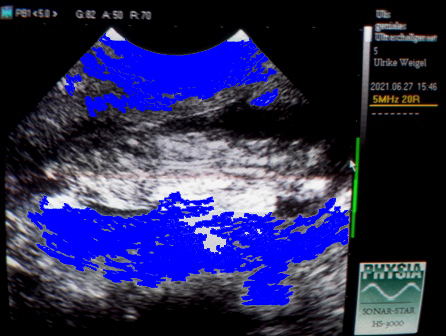

Gestern konnte ich mich nicht bremsen und hab sie nochmal besucht :)

Ich hab mal alles drumherum, wo nichts ist, blau gemacht,

in der Mitte quer seht ihr die Fruchthülle, darin der Welpe :) :)

Wahnsinn, wie sie gewachsen sind! Es ist die gleiche Einstellung wie immer!!

Links seht ihr den Kopf und dann nach rechts den Rücken.

Wir gucken quasi gerade von oben drauf...

Sie sind ganz schön munter! Herrlich :)